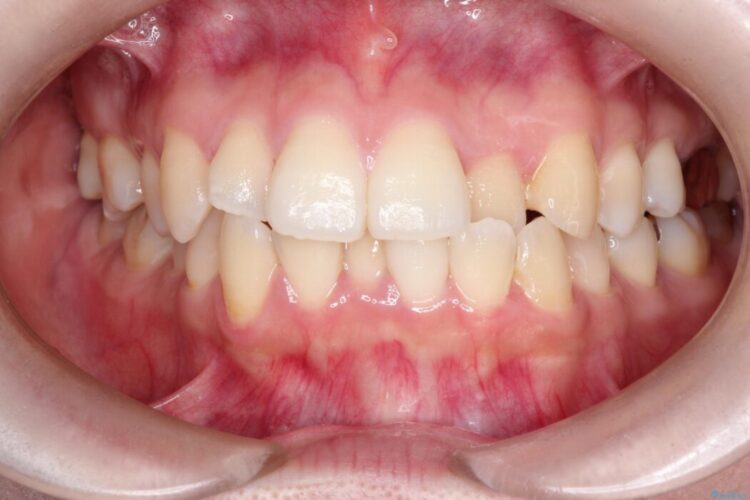

口元を下げて前突感を無くしたい、下の歯の凹凸も無くしたいとご来院された患者様です。

アゴの骨格的なズレがあったため、歯の真ん中を完全に合わせることは不可能と説明。上下4本抜歯を行い、ワイヤー矯正で噛み合わせの大きな改善を目指しました。